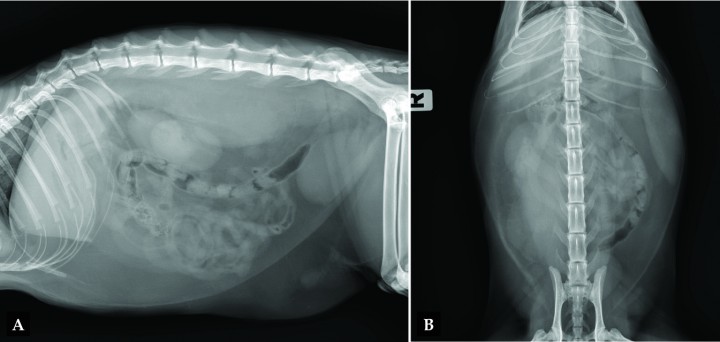

Se realizan radiografías de abdomen lateral (L) y ventrodorsal (Fig. 1) para investigar posibles causas del dolor abdominal y la fiebre asociada.

<p>(A) Radiografía lateral y (B) ventrodorsal de abdomen de un gato que se presenta con dolor abdominal.</p>

(A) Radiografía lateral y (B) ventrodorsal de abdomen de un gato que se presenta con dolor abdominal.